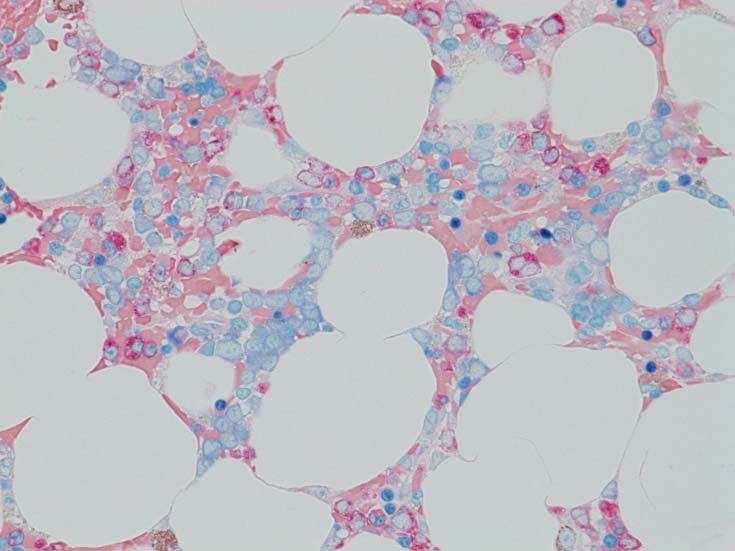

骨髄赤芽球のHbF発現

MDS症例のHbF発現.

サムネイル画像をクリックすると大きな画像が見られます.

MDSでの赤芽球HbF発現は, 陽性細胞はそれほど多くない印象ですが, この低形成性MDS症例では, 多くの陽性細胞がaggregatesを形成していました.